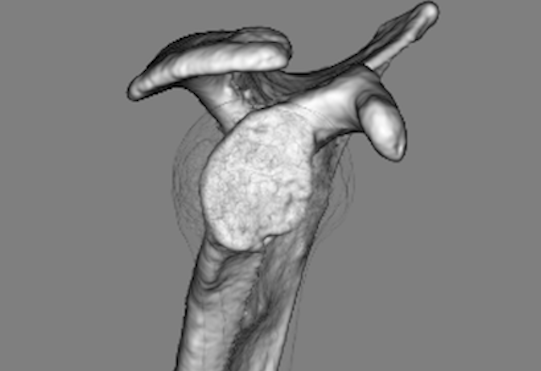

| 術前:骨性Bankart病変 | 術後約6ヶ月 |

|

現病歴:ソフトテニス中に右肩関節を外転外旋位でボールを打ち返した歳に脱臼感が出現しました。佐久平整形外科クリニック受診し右肩関節唇損傷の疑いで3ヶ月間リハビリテーションを行いましたが、症状改善なく造影MRI検査施行し、結果より前方関節唇損傷・骨性Bankart病変と診断されました。疼痛・脱臼感などの症状改善がみられず競技継続を希望されたため、鏡視下肩関節唇形成術を施行し、その術中で遊離体を発見したため摘出術も施行しました。

2016年4月にソフトテニス中に右肩関節を外転外旋位でボールを打ち返した際に脱臼感があり、自己整復をした上で、佐久平整形外科クリニックを受診されました。右肩関節唇損傷の疑いと診断し約3ヶ月間リハビリテーションを行いました。しかし、症状改善がなく造影MRI検査を施行し、結果より前方関節唇損傷と骨性Bankart病変と診断されました。ソフトテニスでのサーブ・スマッシュ時の疼痛・脱臼感などの症状が改善されず、今後も競技を続けるために手術を決められました。